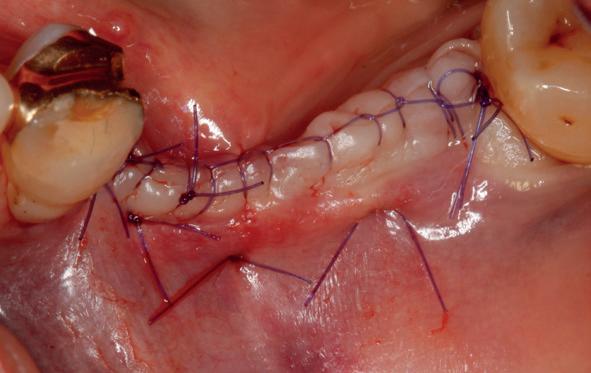

Na 4 weken intra-orale scan voor de etsbrug en kleurbepaling bij de technicus

• Plaatsen van de etsbrug met een composietcement

Voordat er gescand kon worden voor een etsbrug, werd een studiemodel vervaardigd om met de technicus te overleggen of er voldoende ruimte was voor 2 centrale incisieven in de mesio-distale zin en of er voldoende ruimte was in occlusie voor de vleugels van de etsbrug. Er hoeft enkel nog aan de 12 en 22 pala-

tinaal geslepen te worden als er geen 1,5 mm ruimte voor de vleugels behaald kan worden. De ruimte was op de dunste plekken 1 mm, dus een kleine preparatie in de 12 en 22 palatinaal was nodig. Omdat de kaak volledig afgevlakt was en dun was geworden, kunnen de dummies van de etsbrug enkel op de kaak “gelegd worden”, maar daarbij zijn er geen papillen en staat de cervicale rand van de dummies net voor de kaak. Een esthetisch resultaat kan daarmee niet behaald worden. Daarom is een aanvulling van de zachte weefsels in de breedte nodig, als het creëren van een emergence profile, waarbij het oogst alsof de gebitselementen uit het weefsel vertrekken.

11. Middels hechtingen het op de juiste plek trekken van het transplantaat

12. Transplantaat ingehecht

13. Occlusaal beeld verdikking van de zachte weefsels

14. Direct postoperatief plaatsen

van de essix met 2 dummy tanden

15. Twee weken post operatief

16. Creëren van een duidelijke indeuking in de mucosa voor emergence profile

17. Genezing van het palatum

18. Etsbrug frontbeeld

19. Etsbrug palatinaal